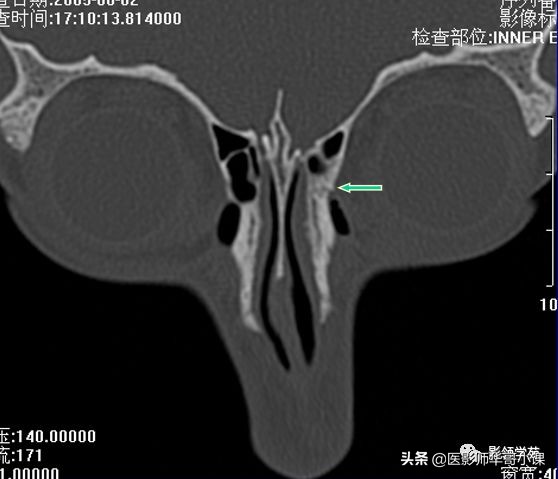

右侧鼻骨骨折

左上颌骨额突骨折

双侧鼻骨骨折

双侧上颌骨额突骨折